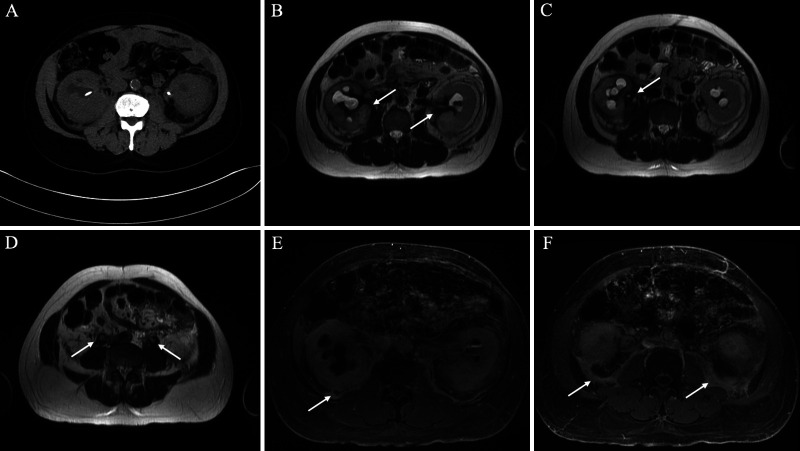

FIG. 3.

Computed tomography (CT) and MRI findings of retroperitoneal fibrosis. A: Axial noncontrast CT shows mildly enlarged kidneys with nonspecific perinephric fat stranding, bilateral hydronephrosis, and partially visualized bilateral ureteral stents. B–D: Axial T2WI shows T2-hypointense signal encasing the kidneys and proximal ureters (arrows). E–F: Postcontrast T1WI shows delayed enhancement of the posterior perinephric space with extension into the posterior pararenal space (arrows). Additionally, there is thickening of the perirenal septa suggesting a “hairy kidney sign” (pathognomonic for Erdheim-Chester disease [ECD]). The constellation of findings is compatible with retroperitoneal fibrosis.